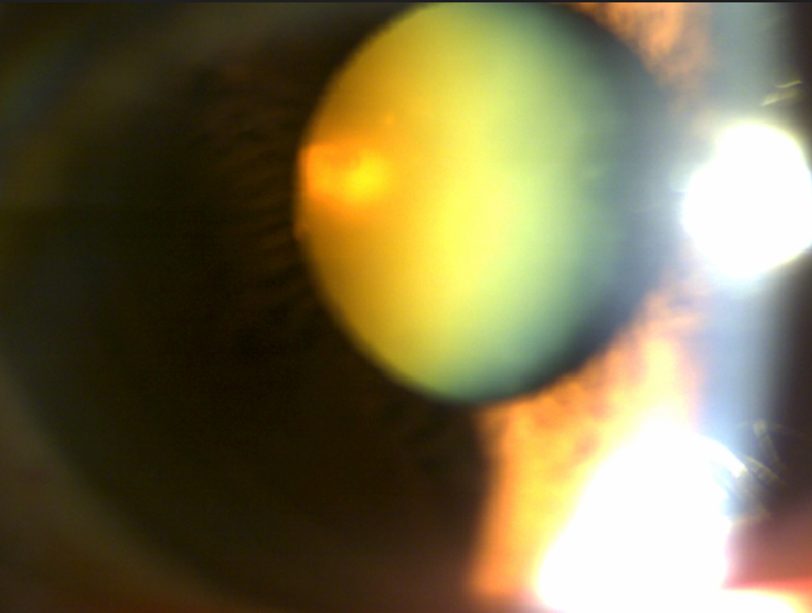

피질백내장 수술

77세 여성 환자 사례

수술 1개월 후 나안시력 0.8

54세 남성 환자 사례

수술 8개월 후 나안시력 0.9

수술 전

수술 후

※ 해당 이미지는 본원에서 직접 촬영한 사진입니다.